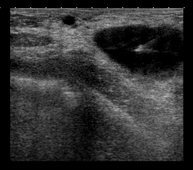

Ecografía mamaria

Es un método de imagen en el que las ondas sonoras crean una imagen de los vasos sanguíneos, tejidos y órganos, incluyendo la mama. La ecografía permite evaluar las anomalías visualizadas en la mamografía o en la exploración clínica, diferenciando asimismo las lesiones sólidas y liquidas (quistes).

PAAF (punción) guiada por ecografía

En la punción aspiración con aguja fina (PAAF) se inserta una aguja fina guiada por ecografía hasta una zona sospechosa de la mama; a continuación se aspira con una jeringa con la que se obtiene escaso material celular que se envía para su estudio citológico. También se utiliza para puncionar y evacuar quistes mamarios y analizar su contenido. Es un procedimiento que dura escasos minutos y produce ligeras molestias.

BAG (biopsia) guiada por ecografía

Biopsia con aguja gruesa o core-biopsia consiste en obtener un cilindro de tejido para estudio histológico. Bajo control ecográfico, y previa anestesia local, se sitúa la aguja en la zona de estudio y, por un sistema de corte automático, se obtienen varios cilindros milimétricos de tejido. Es un procedimiento relativamente corto y escasamente doloroso. Permite obtener una muestra importante para poder realizar un estudio histológico.